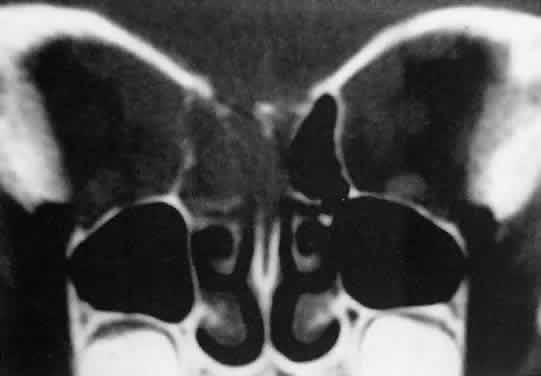

energy, the amplitude of the spikes falls off somewhat through the lesion (see Fig. 1B and C). MRI can help define the tumor's relationship to extraocular muscles (Fig. 2).  Fig. 1. A. Proptosis and downward, outward globe displacement developed over 2 days

in a 3-year-old girl. A homogeneous mass fills the superomedial orbit. B. Contact B-scanning shows a relatively well-circumscribed mass with uniform

internal echoes. C. Contact A-scanning shows the internal reflectivity to be of low to medium

amplitude, consistent with a sarcomatous lesion. Biopsy results confirmed

the diagnosis of rhabdomyosarcoma. Fig. 1. A. Proptosis and downward, outward globe displacement developed over 2 days

in a 3-year-old girl. A homogeneous mass fills the superomedial orbit. B. Contact B-scanning shows a relatively well-circumscribed mass with uniform

internal echoes. C. Contact A-scanning shows the internal reflectivity to be of low to medium

amplitude, consistent with a sarcomatous lesion. Biopsy results confirmed

the diagnosis of rhabdomyosarcoma.